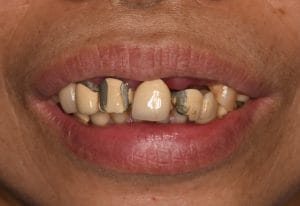

62歲患者h小姐上排因假牙相連,不易清潔導致牙周問題,牙齒陸續搖晃,之前做的假牙時間較久外部燒陶瓷部